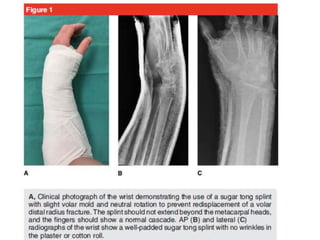

Incruento

• Fracturas no desplazadas se pueden tratar con reducción cerrada e

inmovilización.

• Yeso en 20º de flexión palmar y desviación cubital.

• Debe evitarse la flexión extrema de la muñeca. (Cotton-Loder)

• Duración de la fijación de yeso 6 semanas

Tiempos en tratamiento incruento

• Valva braquipalmar posterior 4 dias

• Yeso cerrado braquipalmar 4 semanas

• Liberacion codo

• Yeso cerrado antebraquipalmar 2 semanas

• Evaluación semanal por varias semanas

EN PACIENTES ANCIANOS

COLOCAR ALGODONADO EN

SITIO DELA MANIOBRA PARA

EL CUIDADO DE LA PIEL

Minimización dela rigidez en la mano